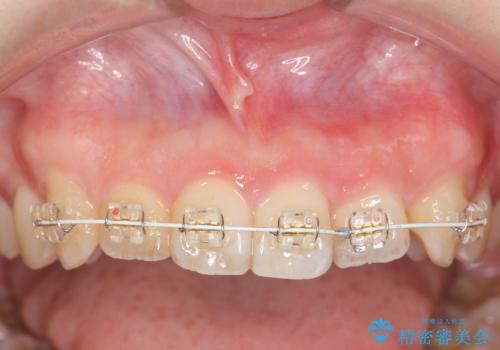

前歯のねじれを改善 小矯正+マウスピース矯正インビザライン

- 「前歯のねじれ、見た目を改善したい。」と矯正治療を希望され来院されました。

マウスピース矯正では改善の難しい前歯のねじれを前歯の部分ワイヤー矯正で改善したのち、インビザライン矯正を行い歯列を整えます。

インビザラインを行う前に前歯の部分矯正を行ったことで、しっかりとねじれが取れ整った歯列へと仕上げることが出来ました。